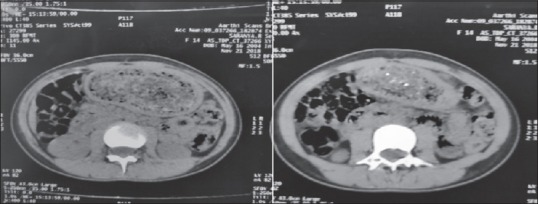

Bezoars are usually defined as collections of nondigestible matter that most commonly accumulates in the stomach and can sometimes extend to the small bowel. Trichobezoars are a rare entity which is most commonly observed in young psychiatric females with trichotillomania and trichophagia. Here, we report a case of giant gastric trichobezoar and a novel technique of laparoscopic removal in a 16 year old female with trichophagia. The giant gastric trichobezoar weighing about half a kilogram was removed en masse laparoscopically by a novel technique. She had an uneventful postoperative recovery and was discharged after psychiatric counseling.